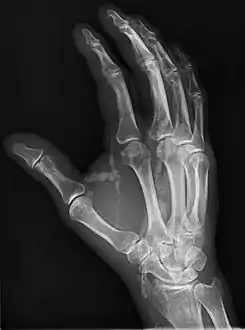

| Hand radiograph showing tumoral calcinosis, PA radiograph of the right hand showing tumoral calcinosis-like metastatic calcification in a patient on dialysis. Dialysis alters calcium phosphate product (>70). Idiopathic tumoral calcinosis is autosomal dominant and is not associated with dialysis. Note the premature arterial calcification which is a clue that this is a renal patient. Vascular calcification contributes to an increase in morbidity. | |

Oblique radiograph of the right hand demonstrating soft tissue calcification, characteristic of dialysis related metastatic calcification.